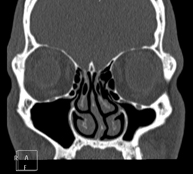

Prova radiològica que consisteix en obtenir imatges del massís facial (cara) d'alta definició anatòmica, mitjançant l'ús d'un equip de TC (Tomografia Computeritzada). Indicacions: tumors, cirurgia plàstica. - TC Oïda

Prova radiològica que consisteix en obtenir imatges dels sins paranasals d'alta definició anatòmica, mitjançant l'ús d'un equip de TC (Tomografia Computeritzada). Indicacions: cefalea, tos crònica, mucositat, infeccions facials. - TC Penyal